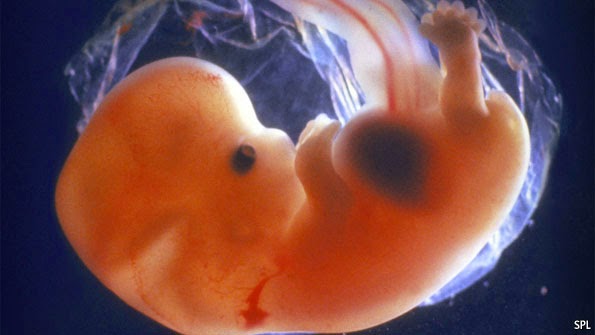

Embrion la examinarea de depistare a sarcinii – la cateva saptamani de intarziere a menstruatiei, cand ecografic se poate evidentia si activitate cardiaca a sa. Evoluţia naturală a unei sarcini poate fi împărţită în două mari categorii :